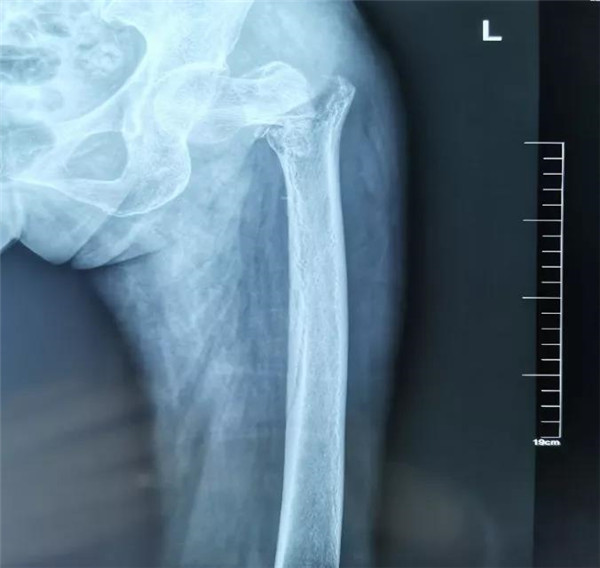

1月前,曲奶奶因在家中不慎跌倒致左髋关节转子间粉碎骨折(图1),在家人的陪同下辗转于西安市多家医院。因曲奶奶年龄较大、身体素质差等原因建议其卧床保守治疗。然而,卧床期间,曲奶奶身体每况愈下,在亲戚朋友的帮助下找到了西安交通大学第一附属医院骨科主任尹战海教授。尹主任看到躺在床上的曲奶奶,也是觉得此刻的老人身体实在太脆弱,患有重度混合型通气功能障碍、骶尾部压疮等多种并发症,加上骨折部位移位较重,手术风险非常高。

(图1.左髋关节X线平片,可见左股骨转子间粉碎性骨折伴移位)